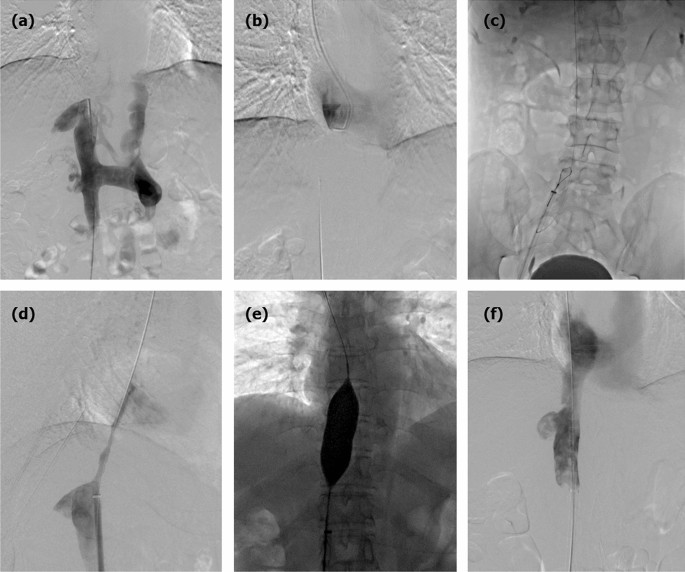

No perioperative deaths were observed. Three complications were observed during recanalization, for a rate of 8.8%. One patient showed contrast agent outflow in the dilated segment after balloon angioplasty. A 26-mm diameter balloon catheter was introduced and dilated immediately to block bleeding, and no contrast agent was exuded after 15 min (Fig. 2). The other patient showed rupture and bleeding of IVC, and surgical repair was performed after failure of balloon blockage. Bleeding of the femoral vein was found in 1 patient (Table 2).

Balloon angioplasty and IVC bleeding. (a) Digital subtraction inferior venography showed a severe stenosis of the proximal IVC. (b) Immediate bleeding was observed in the dilated segment after balloon angioplasty. (c) The 26 mm diameter balloon catheter was introduced and dilated immediately to block bleeding. (d) Venography showed the disappearance of bleeding after 15 min without further management.